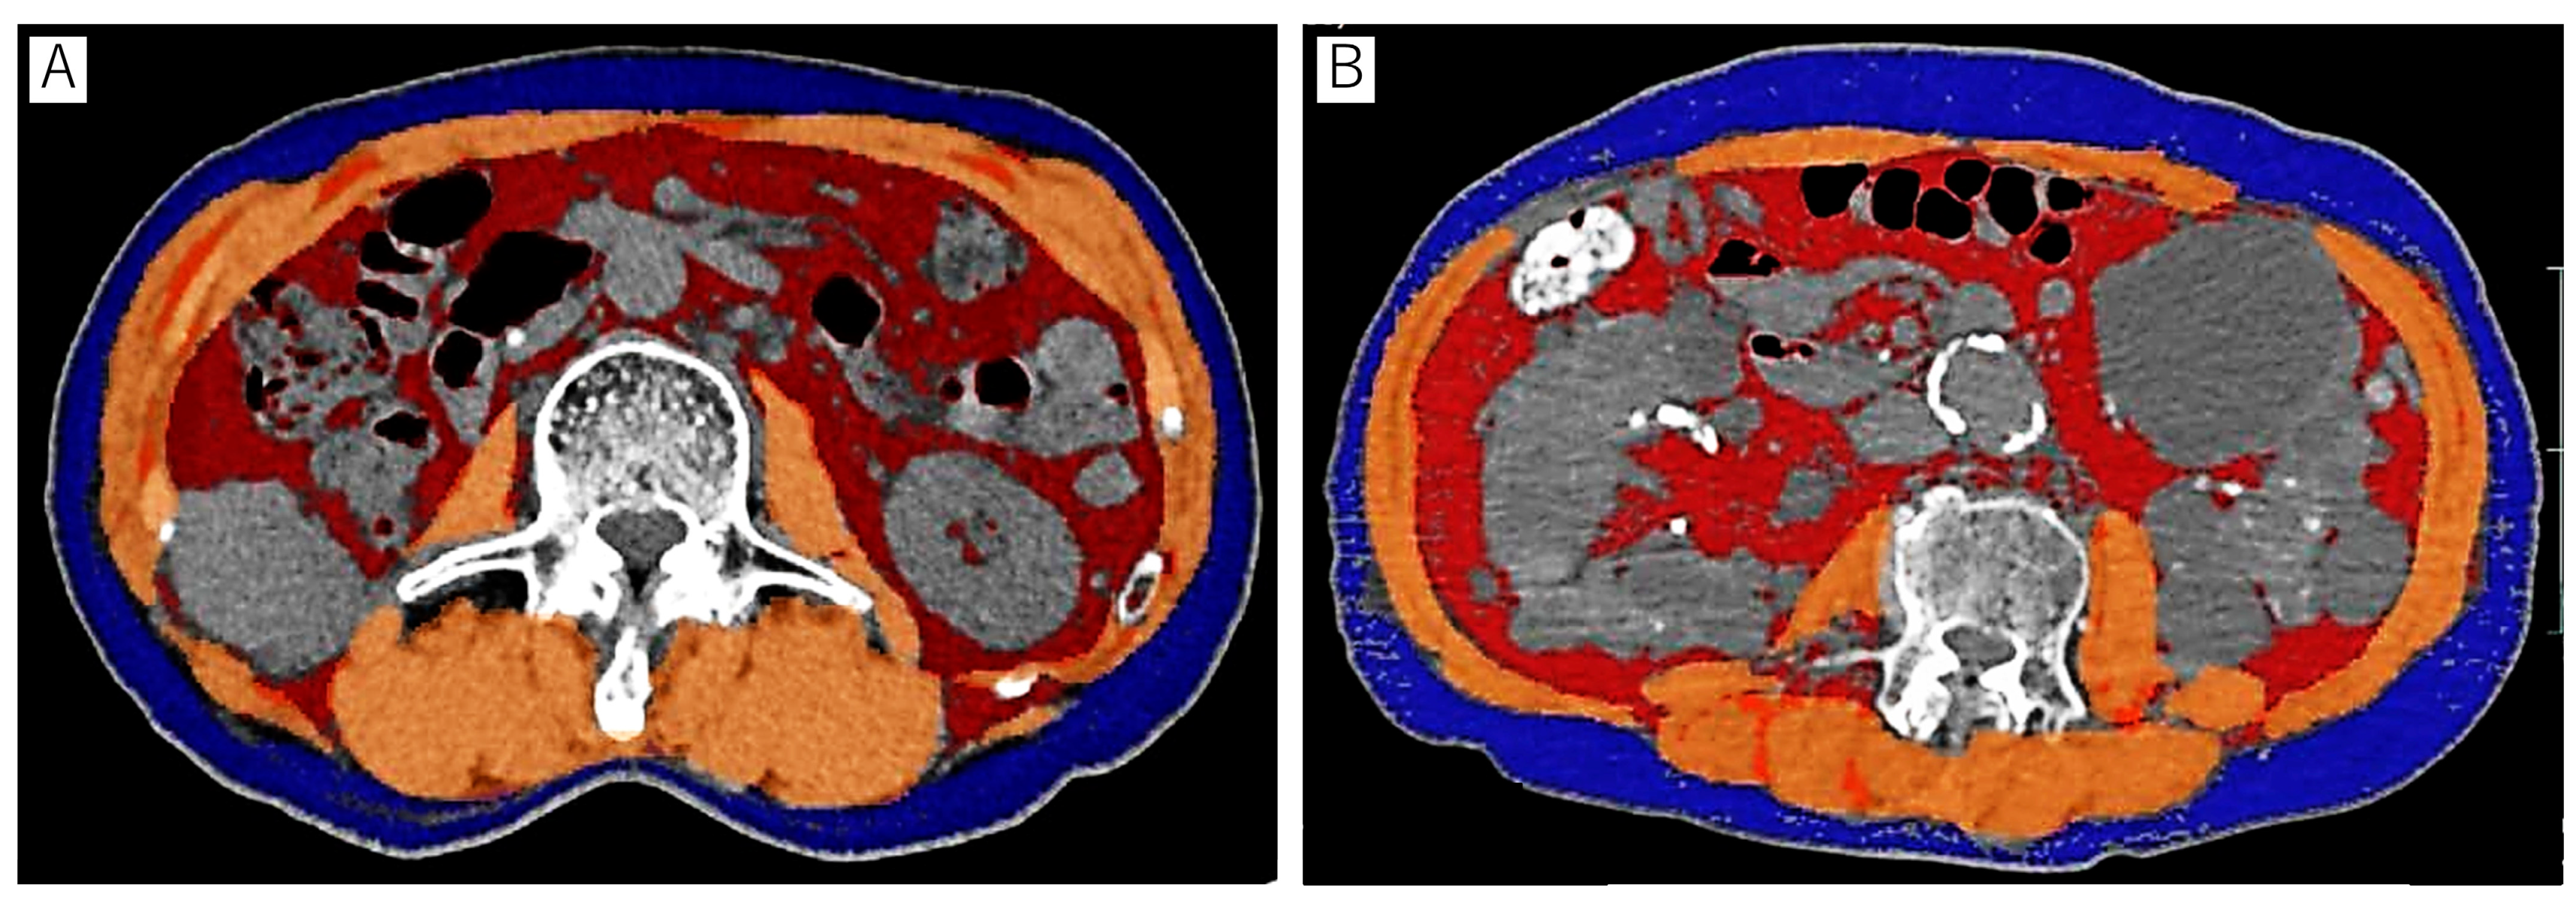

2.2. Body Composition Analysis